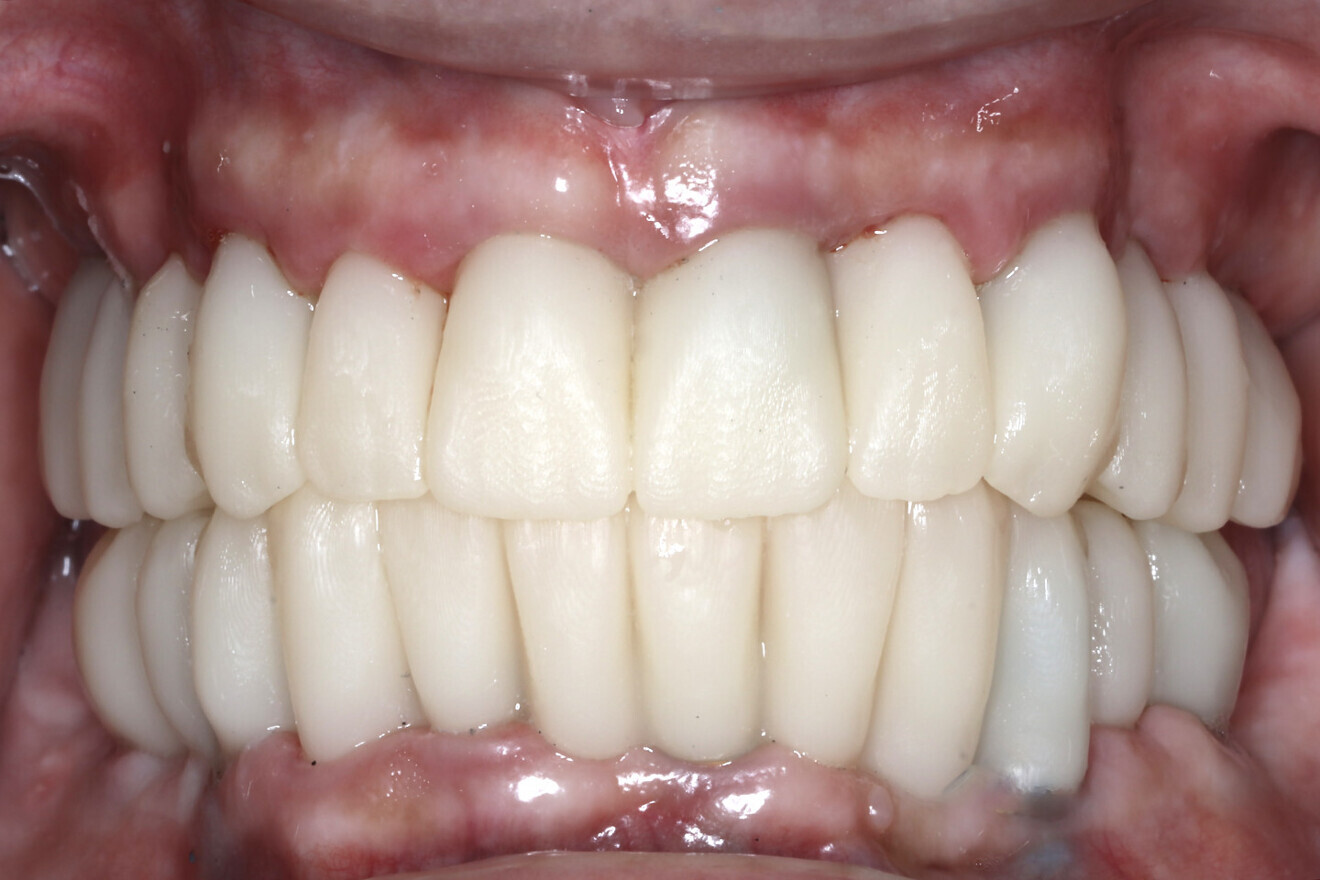

Fig. 17b: Retracted intra-oral view.

The data collected was sent through a scanning software portal (Medit Scan for Clinics) to the dental laboratory with requested changes for correction of the desired smile design. Utilising advanced planning features in the design software (exocad), the midline and tooth size changes were corrected. 3D-printed maxillary and mandibular PMMA restorations were used for try-in using the direct-to-MUA screws (Vortex LA VIS; Fig. 16a). Fit, phonetics, aesthetics and occlusion were evaluated and confirmed using digital articulation (OccluSense; Fig. 16b). The patient was extremely satisfied with the printed try-ins. Since no adjustments were required, the patient was allowed to leave with the printed try-ins as new provisional restorations made from extra-strong resin. The new provisional restorations were worn for ten days to confirm form and function. The final shade was chosen, and metal-free monolithic zirconia restorations were then fabricated by the laboratory.

The final restorations were passively and accurately seated ten days later uneventfully using Vortex LA VIS screws. Confirmation records were taken with photographs, radiographs and digital articulation to recheck fit, function, phonetics and occlusion (Fig. 17a). The patient was extremely satisfied with his final restorations, describing the process as life-changing and surprisingly fast in comparison with what he had heard about full-mouth implant therapy. He was especially pleased with the speed at which the final process was able to be completed (Figs. 17b & c).